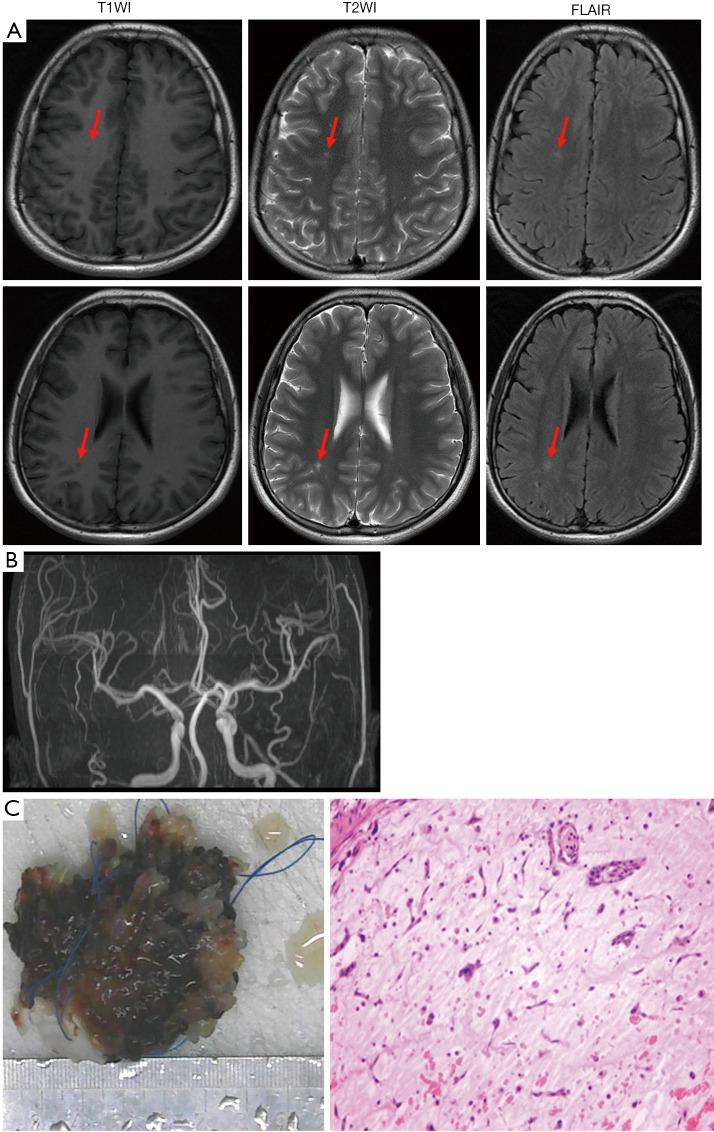

Intracranial aneurysm may appear even after the removal of the cardiac myxoma. However, the pathogenesis and treatment of such aneurysm lesions are not clear. The study aimed to explore the clinical and imaging manifestation, hypothetical pathogenesis, and therapy in one case of left atrial myxoma causing multiple intracranial aneurysms. A 14-year-old male displayed a 3-hour history of episodic loss of consciousness and right hemiplegia after a leapfrog-like movement. The myxoma was diagnosed by a combination of clinical examination, leading to the diagnosis of mitral dynamic obstruction with a Grade III mitral diastolic murmur and tumor plop; magnetic resonance imaging, revealing multiple ischemic sites in both semi-oval centers; and transthoracic echocardiography, demonstrating a mitral valve obstruction. The myxoma was removed surgically; however, computed tomography angiography showed multiple intracranial aneurysms in both middle cerebral arteries 18 months after resection of the atrial myxoma. After conservative treatment, the patient had no neurological dysfunction symptoms for 5 years after myxoma resection. His condition is relatively stable. In conclusion, resection of the atrial myxoma may eliminate the early neurological symptoms, but it cannot ensure the nonoccurrence of delayed intracranial aneurysms. The neoplastic process theory was favored for explaining the aneurysm development in this case. According to the specific conditions of the patient, a combination of open surgery, chemotherapy, radiotherapy, and coil embolization is recommended.

即使切除心脏黏液瘤后仍可能出现颅内动脉瘤。然而,此类动脉瘤病变的发病机制和治疗方法尚不清楚。本研究旨在探讨1例左心房黏液瘤导致多发颅内动脉瘤患者的临床及影像学表现、可能的发病机制和治疗方法。一名14岁男性在进行蛙跳样运动后出现3小时的发作性意识丧失和右侧偏瘫病史。通过临床检查、伴有III级二尖瓣舒张期杂音和肿瘤扑落音的二尖瓣动态梗阻诊断、磁共振成像显示双侧半卵圆中心多个缺血部位以及经胸超声心动图显示二尖瓣梗阻等综合手段确诊为黏液瘤。手术切除了黏液瘤;然而,心脏黏液瘤切除术后18个月的计算机断层扫描血管造影显示双侧大脑中动脉多发颅内动脉瘤。保守治疗后,患者在黏液瘤切除术后5年无神经功能障碍症状。其病情相对稳定。总之,切除心房黏液瘤可能消除早期神经症状,但不能确保不发生延迟性颅内动脉瘤。肿瘤形成过程理论更有利于解释该病例中动脉瘤的发生发展。根据患者的具体情况,建议采用开放手术、化疗、放疗和弹簧圈栓塞相结合的治疗方法。